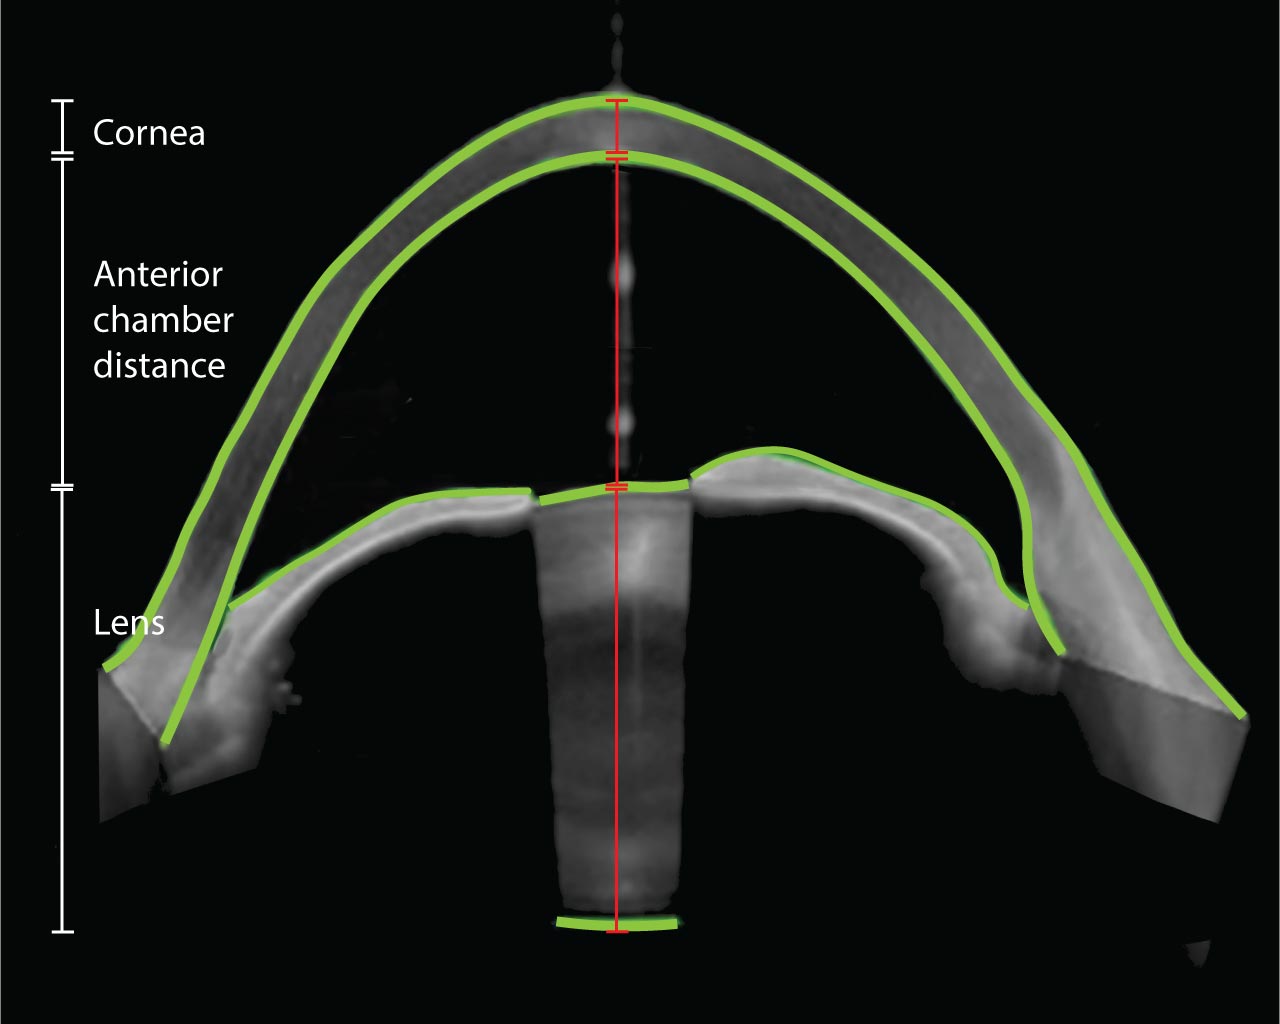

Hornhäute mit Keratokonus sind in der Regel dünner als normale Hornhäute. Sofern sie aber nicht extrem dünn sind, sollte dies keinen Einfluss auf die technischen Schwierigkeiten des Eingriffs haben. Bei ELZA können wir die Option anbieten, die Kataraktchirurgie mit einem Femtosekundenlaser zu unterstützen. Dabei macht der Laser superpräzise Schnitte in die Hornhaut, führt eine Kapsulotomie durch und fragmentiert die Linse vor, um den gesamten Eingriff so sicher und sanft wie möglich zu gestalten. Dieser Ansatz sollte in Betracht gezogen werden, wenn Augen mit sehr dünner Keratokonus-Hornhaut eine Kataraktoperation erfordern.